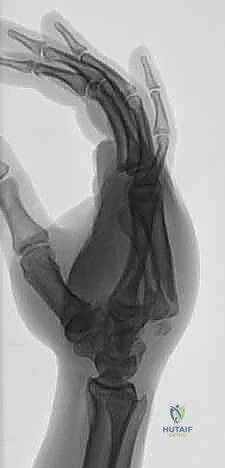

يُعتبر التشخيص الدقيق هو حجر الزاوية في نجاح العلاج. المشكلة الكبرى في كسور وخلع مفصل الكربوميتاكاربال هي أن التراكب التشريحي لعظام الرسغ والمشط في صور الأشعة السينية الأمامية الخلفية (AP View) العادية يجعل من الصعب جداً رؤية الخلع.

- صور الأشعة السينية المتخصصة (X-Rays): لا يكتفي الدكتور بالصور التقليدية، بل يطلب وضعيات تصوير خاصة (مثل الوضعية المائلة Oblique View بـ 30 درجة) التي تظهر قاعدة المشط بوضوح وتكشف الخلع الخفي.

- الأشعة المقطعية (CT Scan): في الحالات المعقدة حيث يكون الكسر مفتتاً أو الخلع متعدداً، يطلب الدكتور أشعة مقطعية ثلاثية الأبعاد (3D CT). هذه التقنية توفر خريطة دقيقة جداً لحجم الشظايا العظمية وتساعد في التخطيط الجراحي بدقة متناهية.